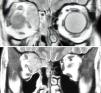

A 25-year-old woman with right subacute sinusitis complained about discomfort in her right eye. Clinical manifestations and computed tomography were suggestive of sub-periosteal orbital ethmoid wall abscess, for which the patient underwent urgent drainage. A solid tumor was found, with a positive biopsy for alveolar rhabdomyosarcoma. Complete remission and resolution of orbital symptoms were achieved with chemotherapy and radiation therapy.

Alveolar orbital rhabdomyosarcoma in adults is uncommon. Rhabdomyosarcoma has a high risk of spreading. It can simulate a sinusitis, as in our patient, early diagnosis and early treatment being especially important in these patients.